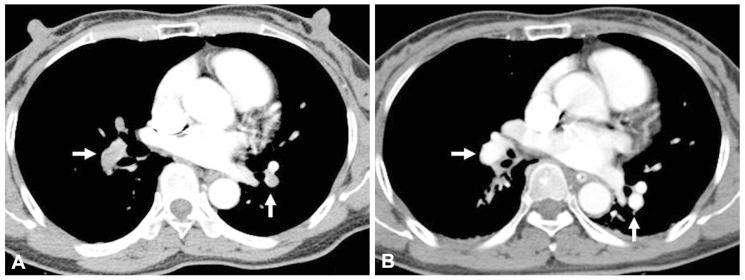

A case of cryptogenic stroke associated with patent foramen ovale coexisting with pulmonary embolisms, deep vein thromboses, and renal artery infarctions.

A paradoxical embolism is defined as a systemic arterial embolism requiring the passage of a venous thrombus into the arterial circulatory system through a right-to-left shunt, and is commonly related to patent foramen ovale (PFO). However, coexisting pulmonary embolisms, deep vein thromboses (DVT), and multipe systemic arterial embolisms, associated with PFO, are rare. Here, we report a patient who had a cryptogenic ischemic stroke, associated with PFO, which is complicated with a massive pulmonary thromboembolism, DVT, and renal infarctions, and subsequently, the patient was treated using a thrombolytic therapy.

矛盾性栓塞定义为静脉血栓通过右向左分流进入体循环动脉系统导致的全身性动脉栓塞,通常与卵圆孔未闭(PFO)有关。然而,PFO 并发肺栓塞、深静脉血栓形成(DVT)和多发性体循环动脉栓塞较为罕见。在此,我们报告了一例伴有 PFO 的隐源性缺血性脑卒中患者,该患者并发了巨大的肺血栓栓塞、DVT 和肾梗死,随后接受溶栓治疗。